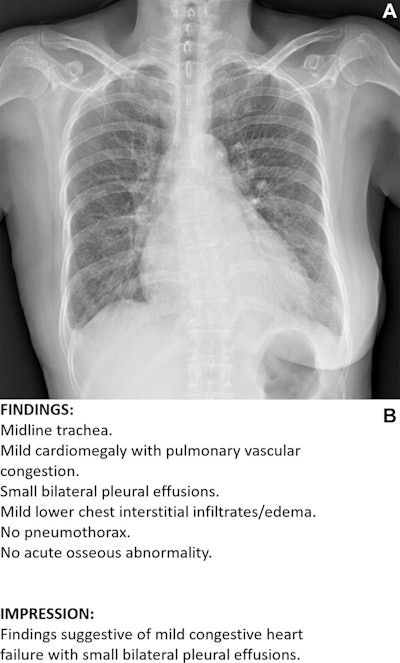

Example of an acceptable AI–generated chest x-ray report. (A) Anteroposterior chest x-ray in a 68-year-old female patient who visited the emergency department because of acute-onset dyspnea shows an enlarged heart, bilateral pleural effusion, and bilateral interstitial thickening, suggesting heart failure and interstitial pulmonary edema. (B) The AI-generated report appropriately describes the findings of the x-ray and suggests a possible diagnosis. All seven thoracic radiologists evaluated the AI-generated report as acceptable without revision.Example of an acceptable AI–generated chest x-ray report. (A) Anteroposterior chest x-ray in a 68-year-old female patient who visited the emergency department because of acute-onset dyspnea shows an enlarged heart, bilateral pleural effusion, and bilateral interstitial thickening, suggesting heart failure and interstitial pulmonary edema. (B) The AI-generated report appropriately describes the findings of the x-ray and suggests a possible diagnosis. All seven thoracic radiologists evaluated the AI-generated report as acceptable without revision. RSNA According to the analysis, there was no evidence of a difference in acceptability between AI-generated and radiologist-written reports under the standard criterion (88.4% versus 89.2%; p = 0.36). However, AI-generated reports were less acceptable than radiologist-written reports under the stringent criterion (66.8% versus 75.7%; p